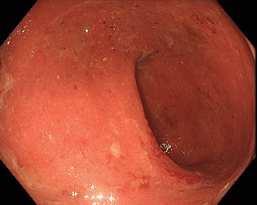

Obr. . Endoskopický nález v levém tra níku – erytém, hlenový povlak, drobné v edy.

Fig. . Endoscopic findings in the left colon – erythema, mucus plaque, small ulcers.